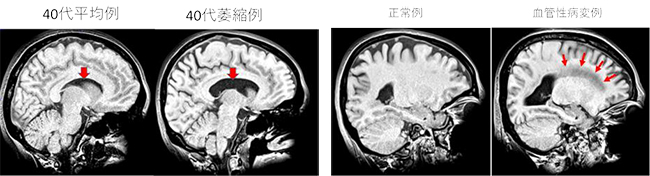

認知症の脳画像診断−早期検出と鑑別をめざして | 西村 恒彦